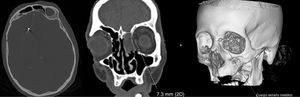

An emergency blood analysis showed leukocytosis (16100cells/mm3) with neutrophilia (89%), lymphocytopaenia (1000cells/mm3), and high levels of fibrinogen (4.72g/L), d-dimer (2645ng/mL), C-reactive protein (5.3mg/L), procalcitonin (0.8ng/mL), and ferritin (401.7ng/mL). A head CT scan showed 2 metallic artefacts in the left nasal region and right frontal lobe, compatible with bird shot (Fig. 1); a chest radiography revealed an interstitial infiltrate in the right lung base and a lumbar puncture yielded turbid cerebrospinal fluid (CSF) with 781leukocytes/μL (predominantly polymorphonuclear, 88%), low glucose levels (3mg/dL), and high protein levels (4.61g/L). Blood cultures and urine pneumococcal and Legionella antigen tests yielded normal results; a PCR test for SARS-CoV-2 returned positive results. CSF microbiology results were positive for Streptococcus pneumoniae. Furthermore, we suspected a CSF fistula; this was confirmed by a facial CT scan.